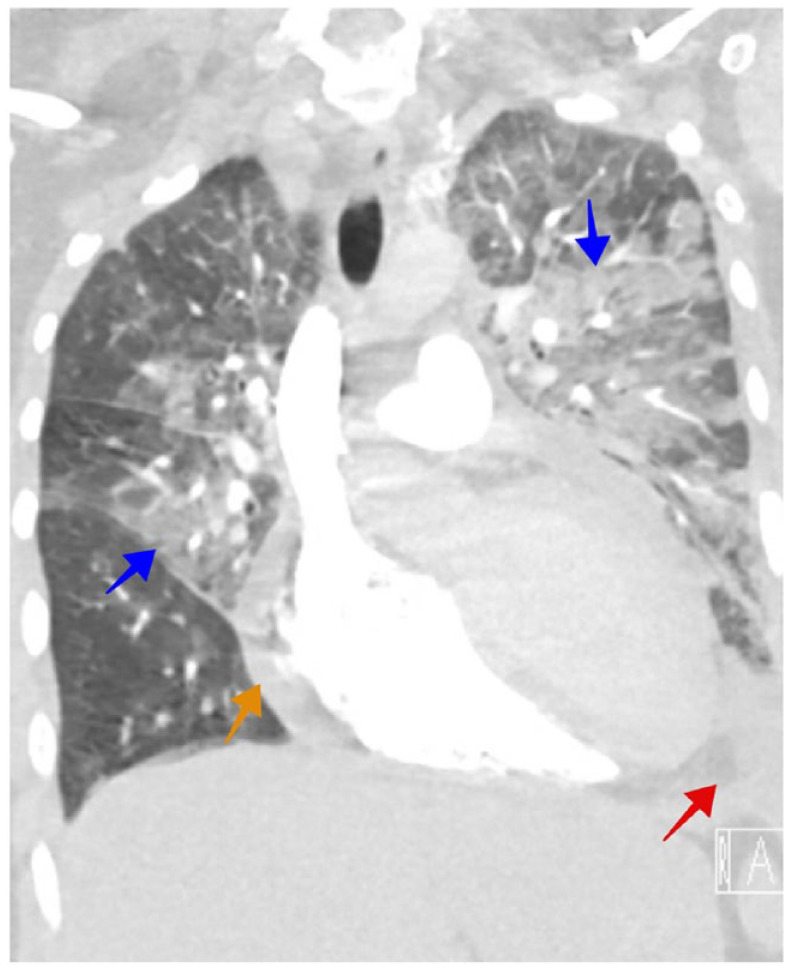

SARS-CoV-2 infection induces myocardiopathy in 19% of severe cases, with a mortality rate of up to 51%. The mainstay of treatment is supportive care, steroids, and tocilizumab (anti-IL-6). This is a case of a 43-year-old woman diagnosed with hormone-positive breast cancer with lung metastasis and pulmonary lymphangitis carcinomatosis (PLC). Her baseline cardiac function was within normal limits. She presented to the emergency department with respiratory distress. Chest CT showed multiple bilateral ground-glass opacities consistent with COVID-19 pneumonia and confirmed by COVID-19-PCR nasal swab. Her condition deteriorated, and she was urgently admitted to the intensive care unit with evidence of a cytokine storm. She was started on tocilizumab, dexamethasone, and meropenem. Echocardiogram (echo) showed a severely reduced ejection fraction with severe global hypokinesis. A second dose of tocilizumab was given, and the dexamethasone dose was increased. Fortunately, the patient had significant clinical and biochemical improvement and regained her normal cardiac function. In conclusion, dexamethasone and tocilizumab could be promising aids in treating cardiomyopathy secondary to SARS-CoV-2 infection.

Abstract Image